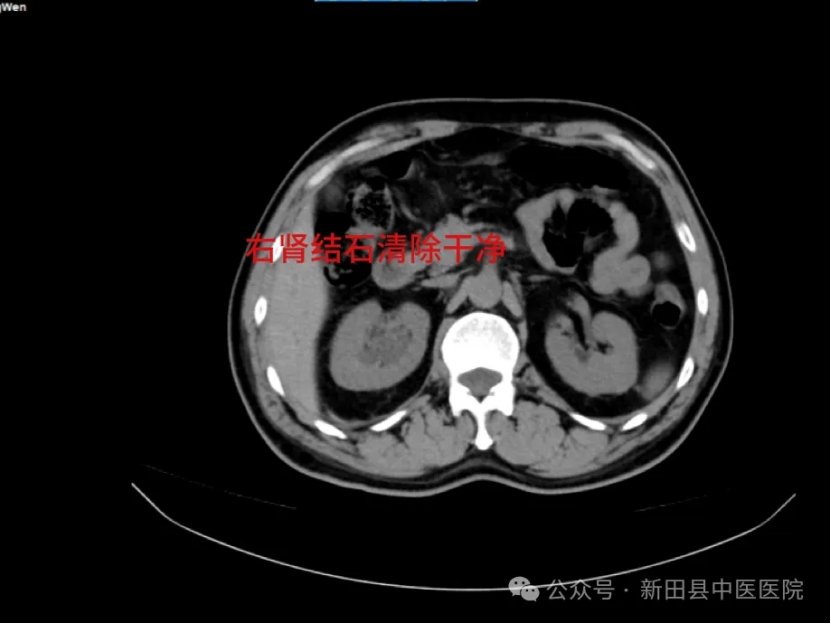

术后影像学检查提示,右肾结石清除干净。一周后,陈女士康复出院时,对邓勇军主任连声称赞。

▲术后CT

术后影像学检查提示:右肾结石清除干净.术后一周患者顺利出院。

术后影像学检查提示:右肾结石清除干净,患者于术后5日顺利出院。